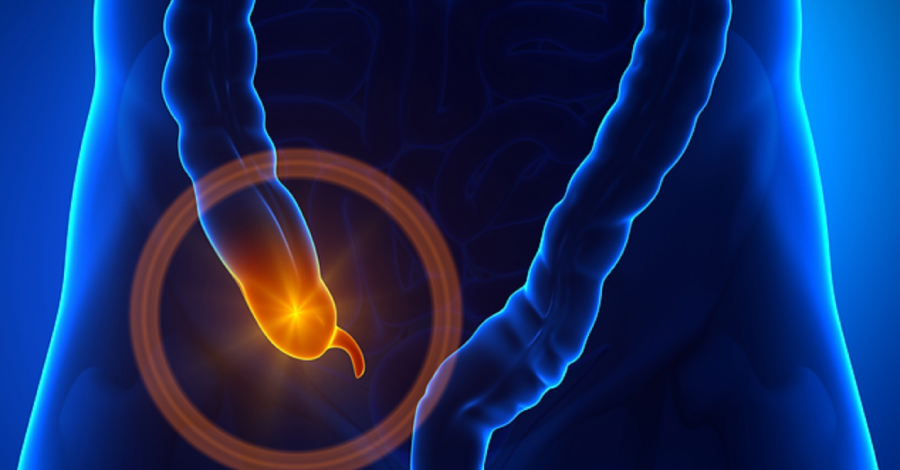

Apendice

• Apendice